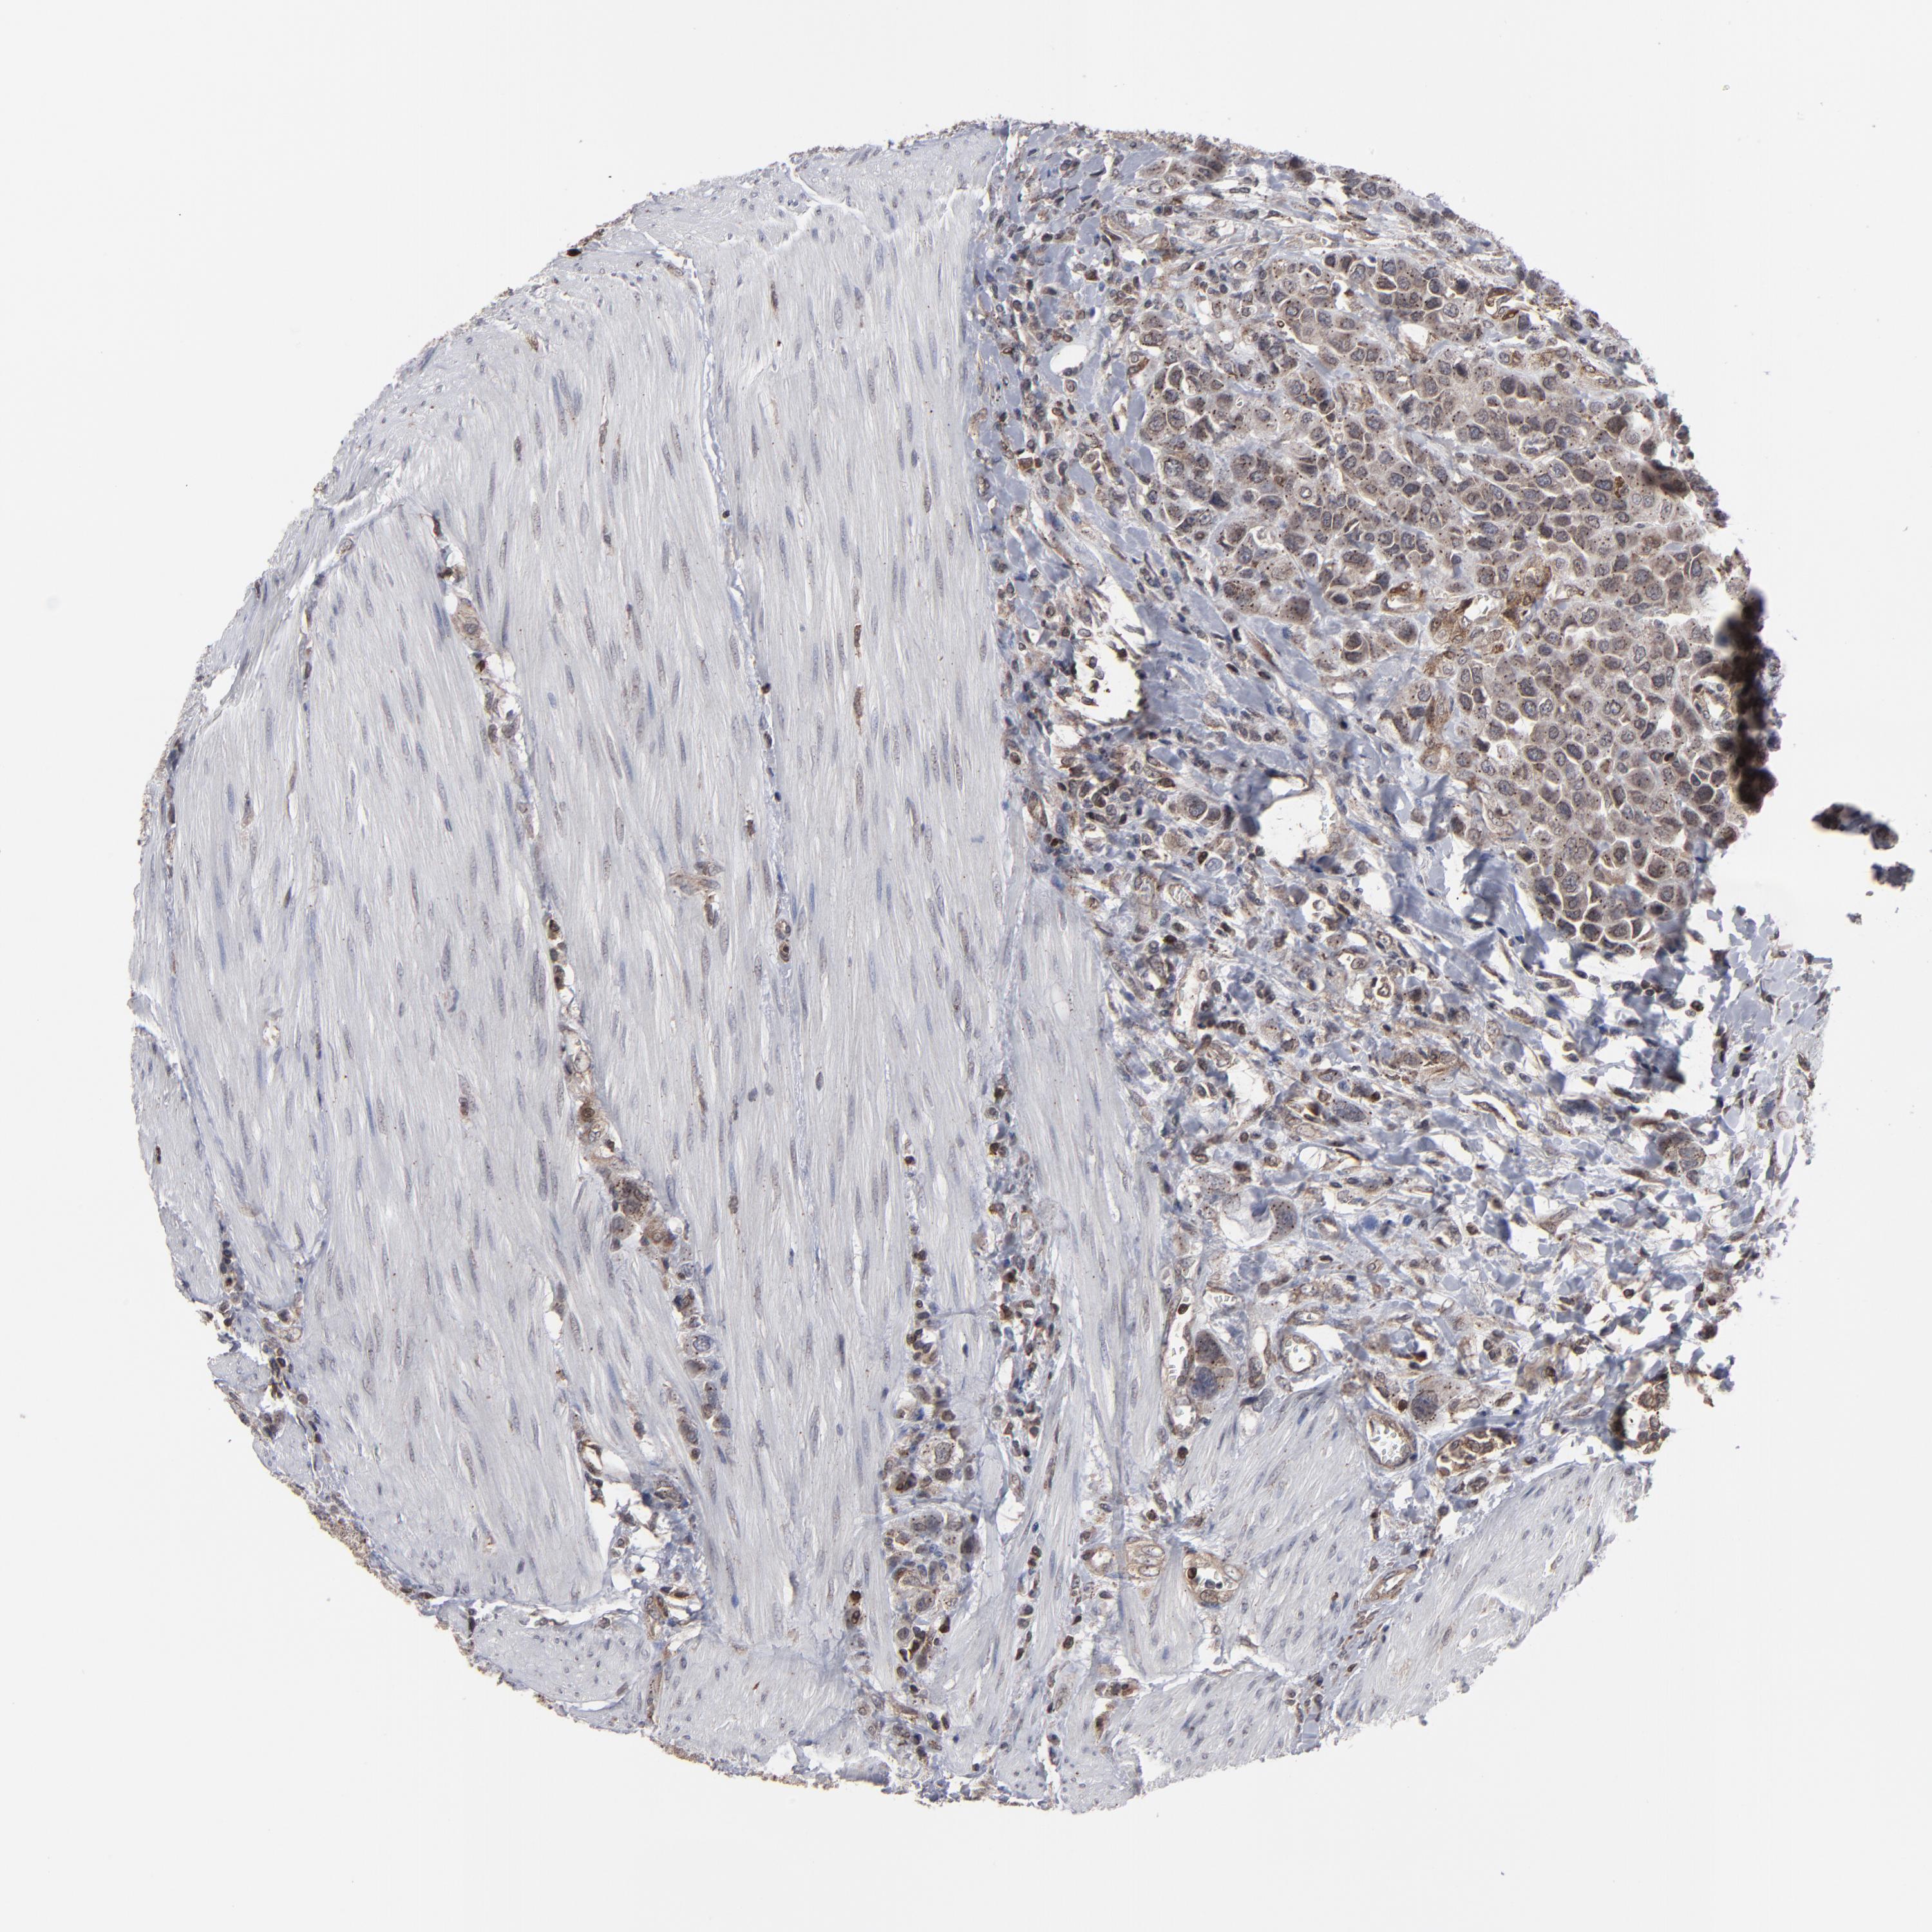

UROTHELIAL CANCER - Protein expressioni

A mouse-over function shows sample information and annotation data. Click on an image to view it in a full screen mode. Samples can be filtered based on level of antibody staining by selecting one or several of the following categories: high, medium, low and not detected. The assay and annotation is described here.

Antibody stainingi

Antibody staining in the annotated cell types in the current human tissue is reported as not detected, low, medium, or high, based on conventional immunohistochemistry profiling in selected tissues. This score is based on the combination of the staining intensity and fraction of stained cells.

Each image is clickable and will lead to virtual microscopy that enables deeper exploration of all samples and also displays staining intensity scores, fraction scores and subcellular localization as well as patient and tissue information for each sample.

Antibody HPA002109

Staining

High

Medium

Low

Not detected

Intensity

Strong

Moderate

Weak

Negative

Quantity

>75%

75%-25%

<25%

None

Location

Nuclear

Cytoplasmic/membranous

Cytoplasmic/membranous,nuclear

Urothelial carcinoma, High grade

Urothelial carcinoma, Low grade